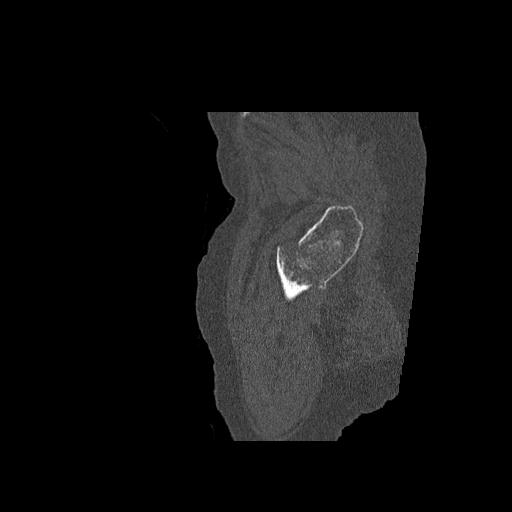

102755 1/4 2R 1/15 2R 右足関節 68歳女性 右三果脱臼骨折